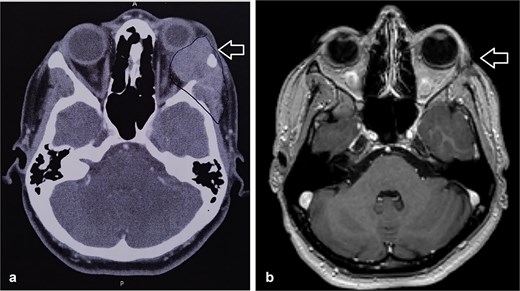

A 27-year-old female patient with no significant medical history presented with a painless lump over the lateral canthus of her left eye. Over several months, the swelling enlarged, causing intermittent, localized pain without numbness, facial palsy, or visual changes. Examination revealed a well-oriented patient with normal cranial nerves and a non-tender left lateral eye swelling. CT scan showed a 3 × 3 × 2.7 cm soft tissue mass with destruction of the lateral orbital wall, while the optic nerve and neck lymph nodes were normal. Biopsy confirmed adenoid cystic carcinoma (ACC).

The patient underwent left orbital transcanthal craniotomy and orbitotomy with resection of the left retro-bulbar tumor. Left neck dissection was conducted with excision of lymph nodes for staging. Assessment of the margin was not performed due to the fragmented nature of the bone, so the patient underwent adjuvant radiotherapy (Fig. 1).

(a) CT scan showed left orbital mass with both solid enhancing and cystic components. The epicenter of the mass appears to be in the left lacrimal gland. (b) MRI postoperative that showed complete tumor excision.